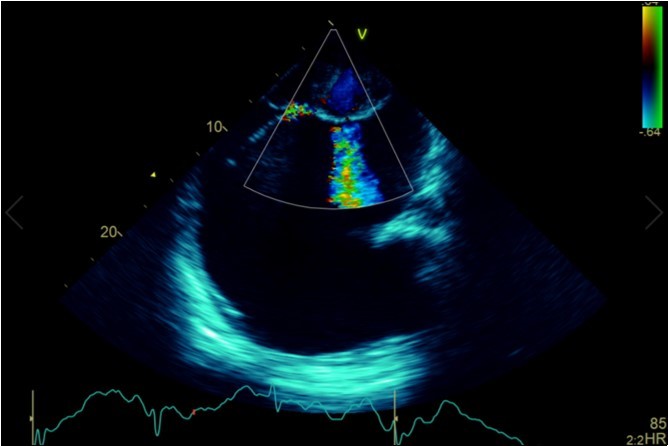

A dramatically dilated left atrium was seen on a TTE (see Figure 2a, Figure 2b, Figure 2c, and Figure 2d). Severe mitral stenosis with associated regurgitation was evident, with a mean gradient across the valve of 11mmHg and a hyperdynamic left ventricle. The left atrial volume measured by Simpson’s biplane method (see Figure 2c) was 2108mL, or 1548.5 ml/m2, based on height 1.55 metres and weight 44 Kg. Normal left atrial volume in a woman is 16 - 34 ml/m21. The computed tomography scan (CT) chest AP view (see Figure 3) is also shown.

Figure 2a.Transthoracic echocardiogram Apical 4C view. Findings include severely enlarged left atrium, severe mitral stenosis with associated regurgitation, a mean gradient across the valve of 11mmHg with a hyperdynamic left ventricle